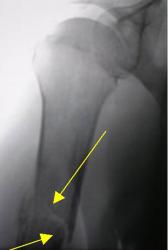

Протокол. На обзорной цифровой флюорограмме правого плечевого сустава (1), произведенной в прямой стандартной проекции, со стороны плечевого сустава изменения возрастного характера. В месте перехода проксимальной трети диафиза в среднюю, на фоне выраженной патологической перестройки структуры костной ткани, определяется линия поперечного «патологического перелома», с некоторым смещением отломков по ширине. Произведена дополнительная цифровая обработка изображения в условиях увеличения изображения и эквилизации (2, 3) для лучшей детализации области перелома.

2. дополнительная цифровая обработка изображения в условиях увеличения изображения и эквилизации